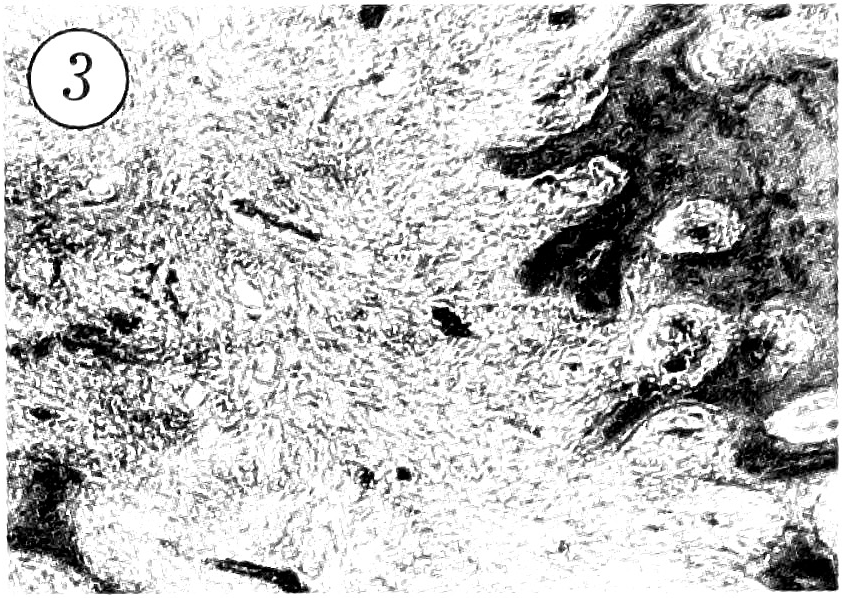

При морфологическом исследовании патологический очаг был представлен фиброзной тканью, окружающей костные трабекулы различной степени зрелости (рис. 3). В центре очага обычно преобладала фиброзная ткань, тогда как костные трабекулы располагались в основном в периферических участках. Фиброзная ткань состояла из относительно рыхло упакованных пучков коллагеновых волокон и клеточных элементов, среди которых превалировали хорошо дифференцированные фибробласты. Пучки коллагеновых волокон иногда формировали «муаровый» рисунок. Из других клеточных элементов в основном определялись гистиоциты и локальные скопления остеокластоподобных гигантских многоядерных клеток. Характерным признаком заболевания была «зональность» архитектоники патологического очага. При этом в центре располагались редкие, относительно тонкие, незрелые трабекулы примитивного или эмбрионального типа, тогда как в периферических участках — более многочисленные, широкие и более зрелые костные трабекулы, имеющие различной степени выраженности пластинчатое строение. В большинстве случаев костные трабекулы были ограничены цепочкой крупных остеобластов с базофильными ядрами (рис. 4).

Рис. 3. В патологическом очаге кортикальная кость замещена фиброзной тканью с отдельными костными трабекулами. Окраска гематоксилином и эозином. Ув. 100.